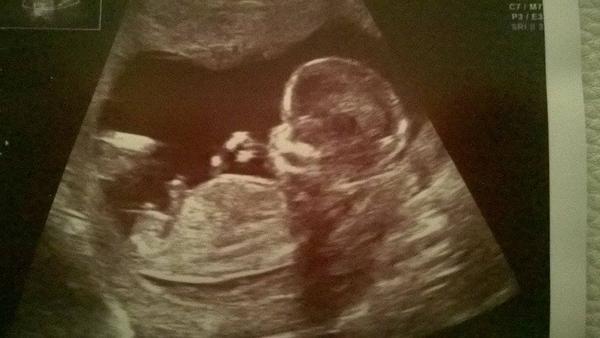

Tak baby môj dnešný test 12dpo

Tu su za radom 7,9,10,12dpo